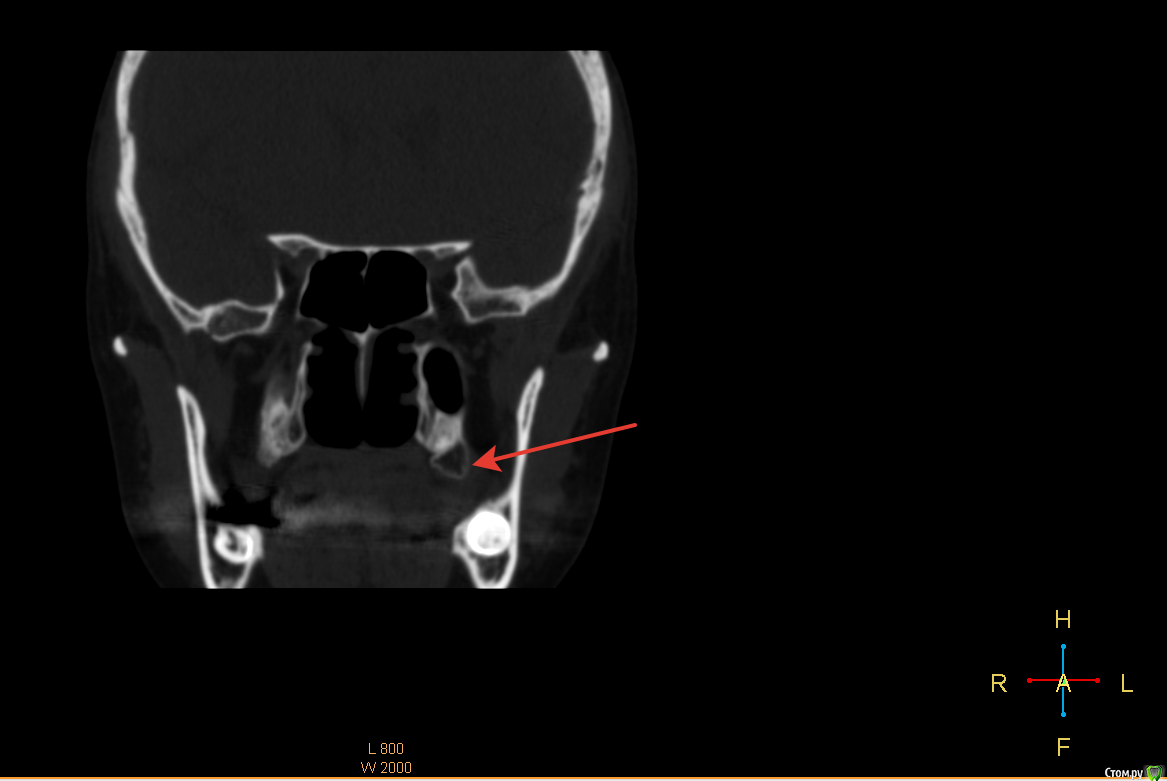

Снежана10 Опубликовано 30 августа, 2017 Автор Поделиться Опубликовано 30 августа, 2017 это я понимаю, а этот мешок на КТ это что? Ссылка на комментарий

red_butler Опубликовано 30 августа, 2017 Поделиться Опубликовано 30 августа, 2017 это я понимаю, а этот мешок на КТ это что?бугор верхней челюсти, кость это 1 Ссылка на комментарий

Снежана10 Опубликовано 30 августа, 2017 Автор Поделиться Опубликовано 30 августа, 2017 а с другой стороны такого нет... Ссылка на комментарий

red_butler Опубликовано 30 августа, 2017 Поделиться Опубликовано 30 августа, 2017 а с другой стороны такого нет...не ищите проблем на пустом месте... 3 Ссылка на комментарий